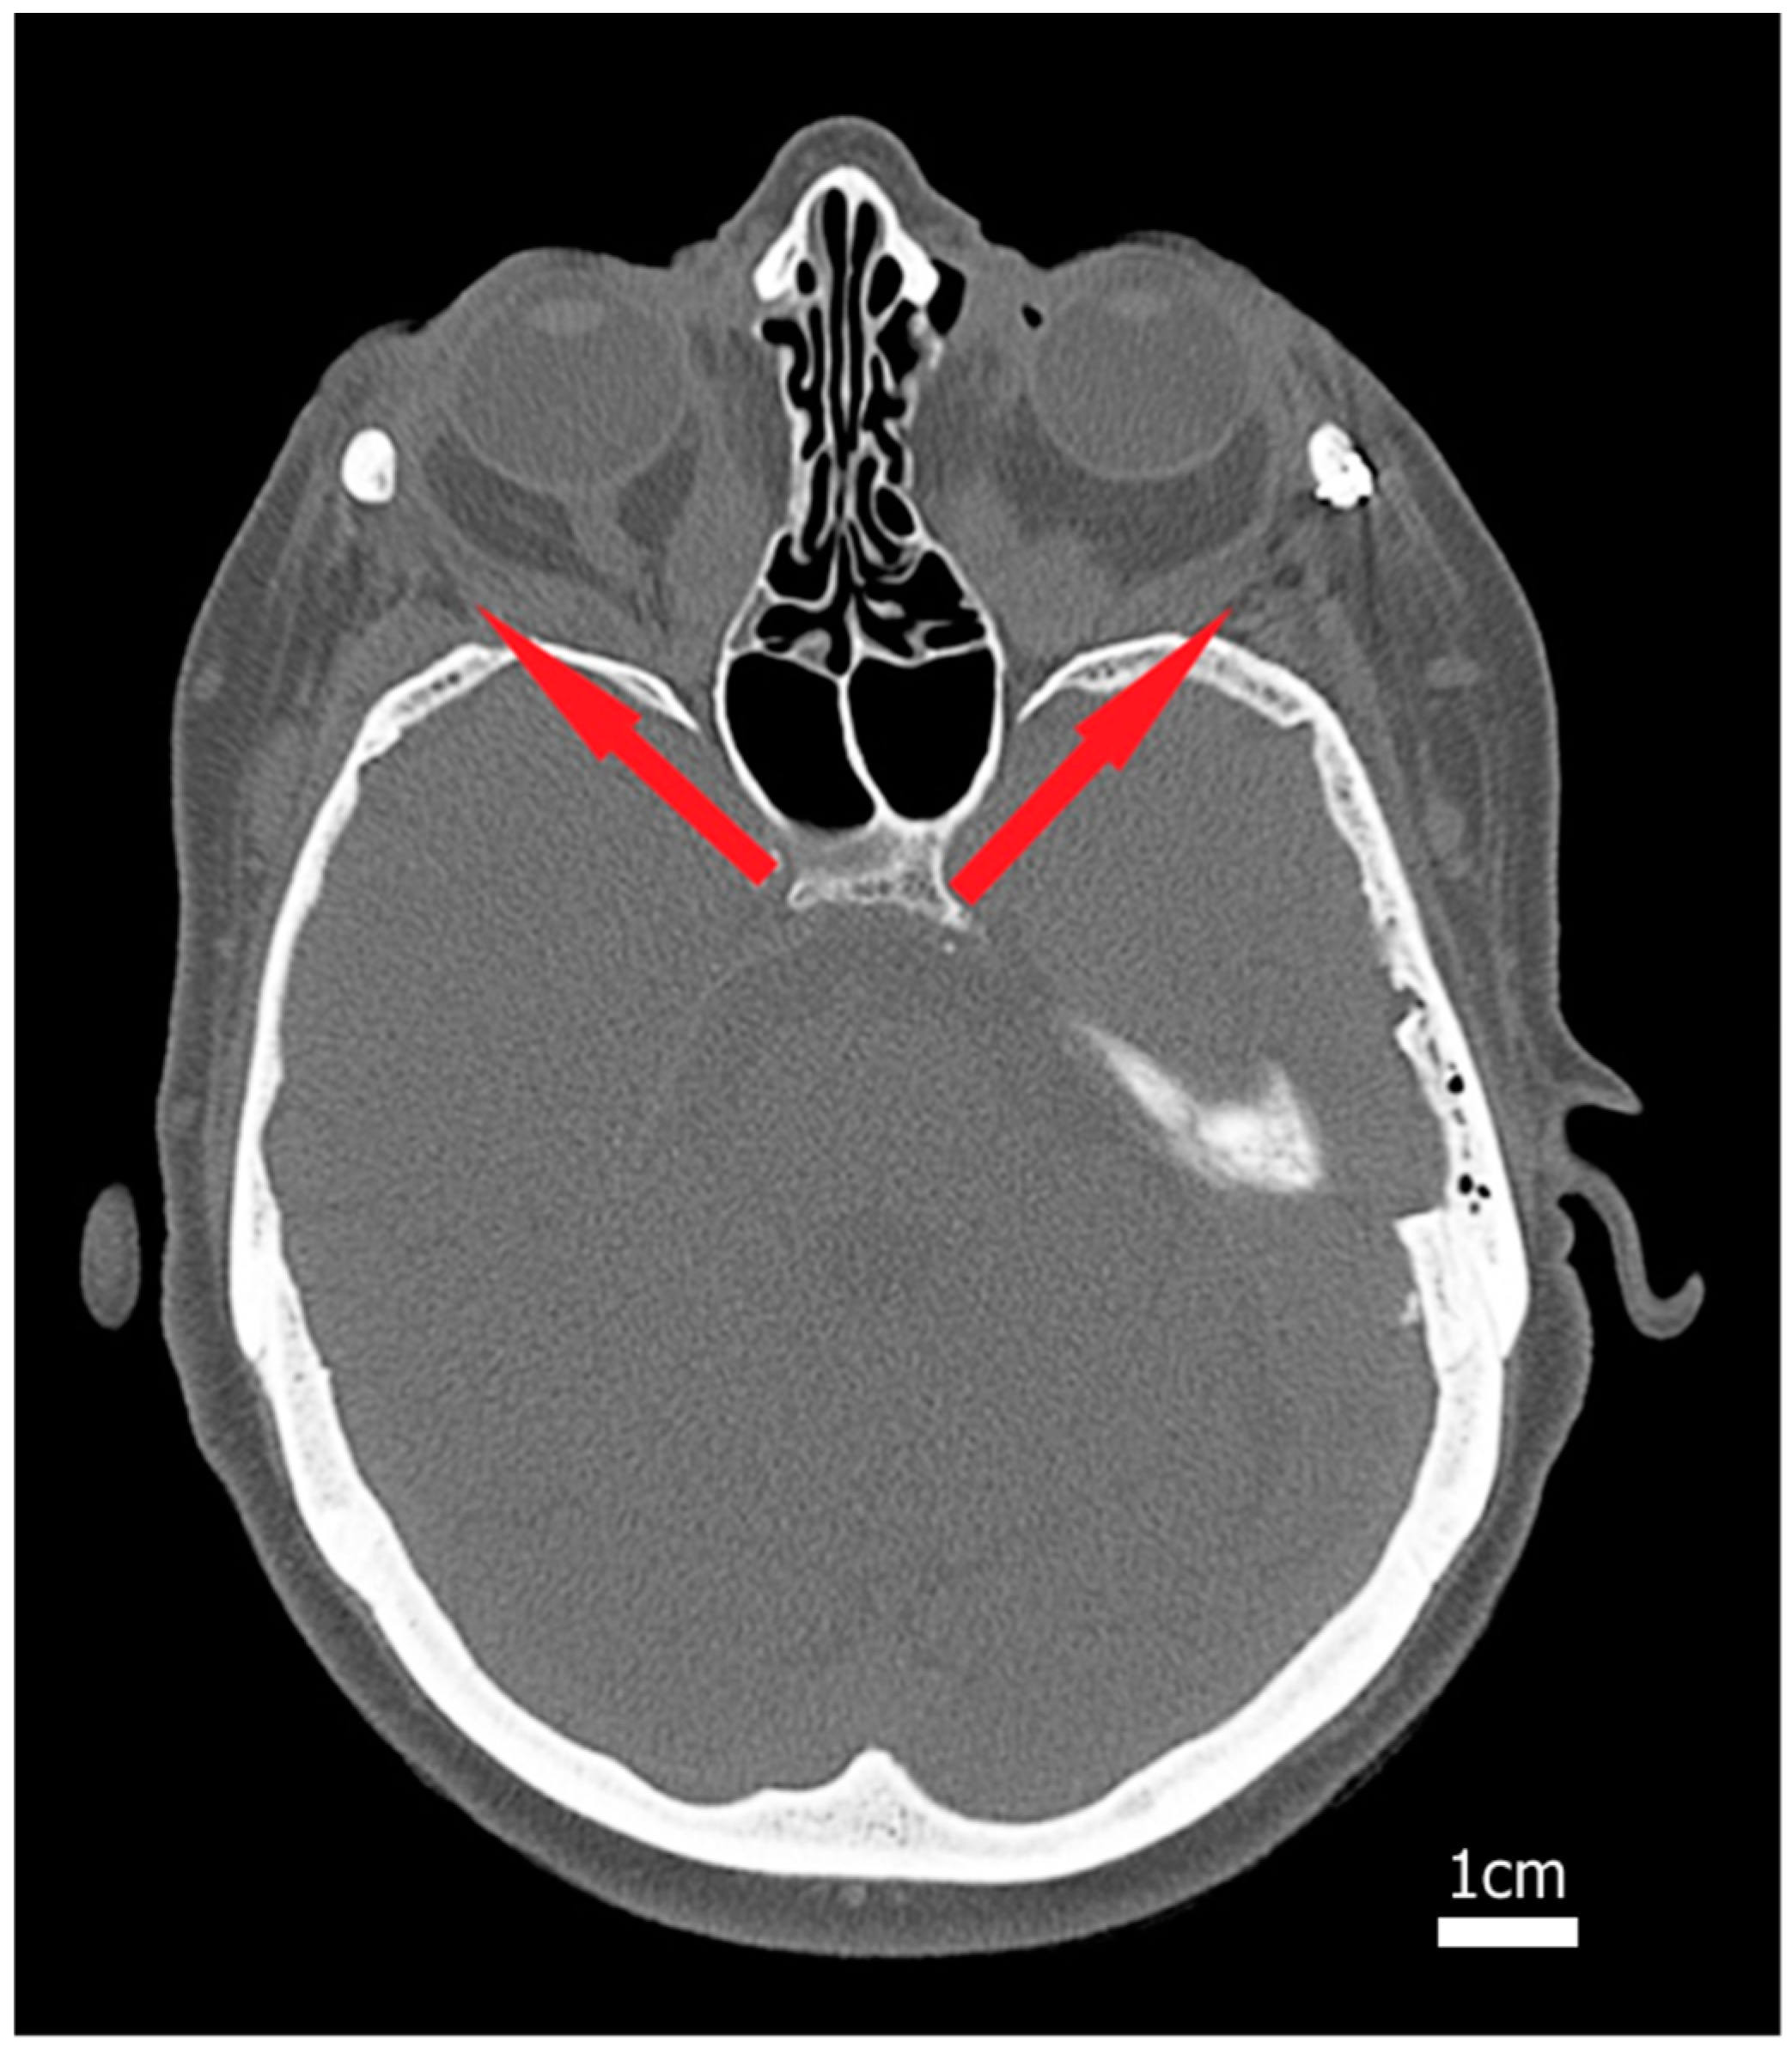

2.1. Surgical Procedure

2.2. Study Design

2.3. Three-Dimensional Image Processing and Orbital Model Generation

2.4. Physics-Based Simulation of Decompression Surgery